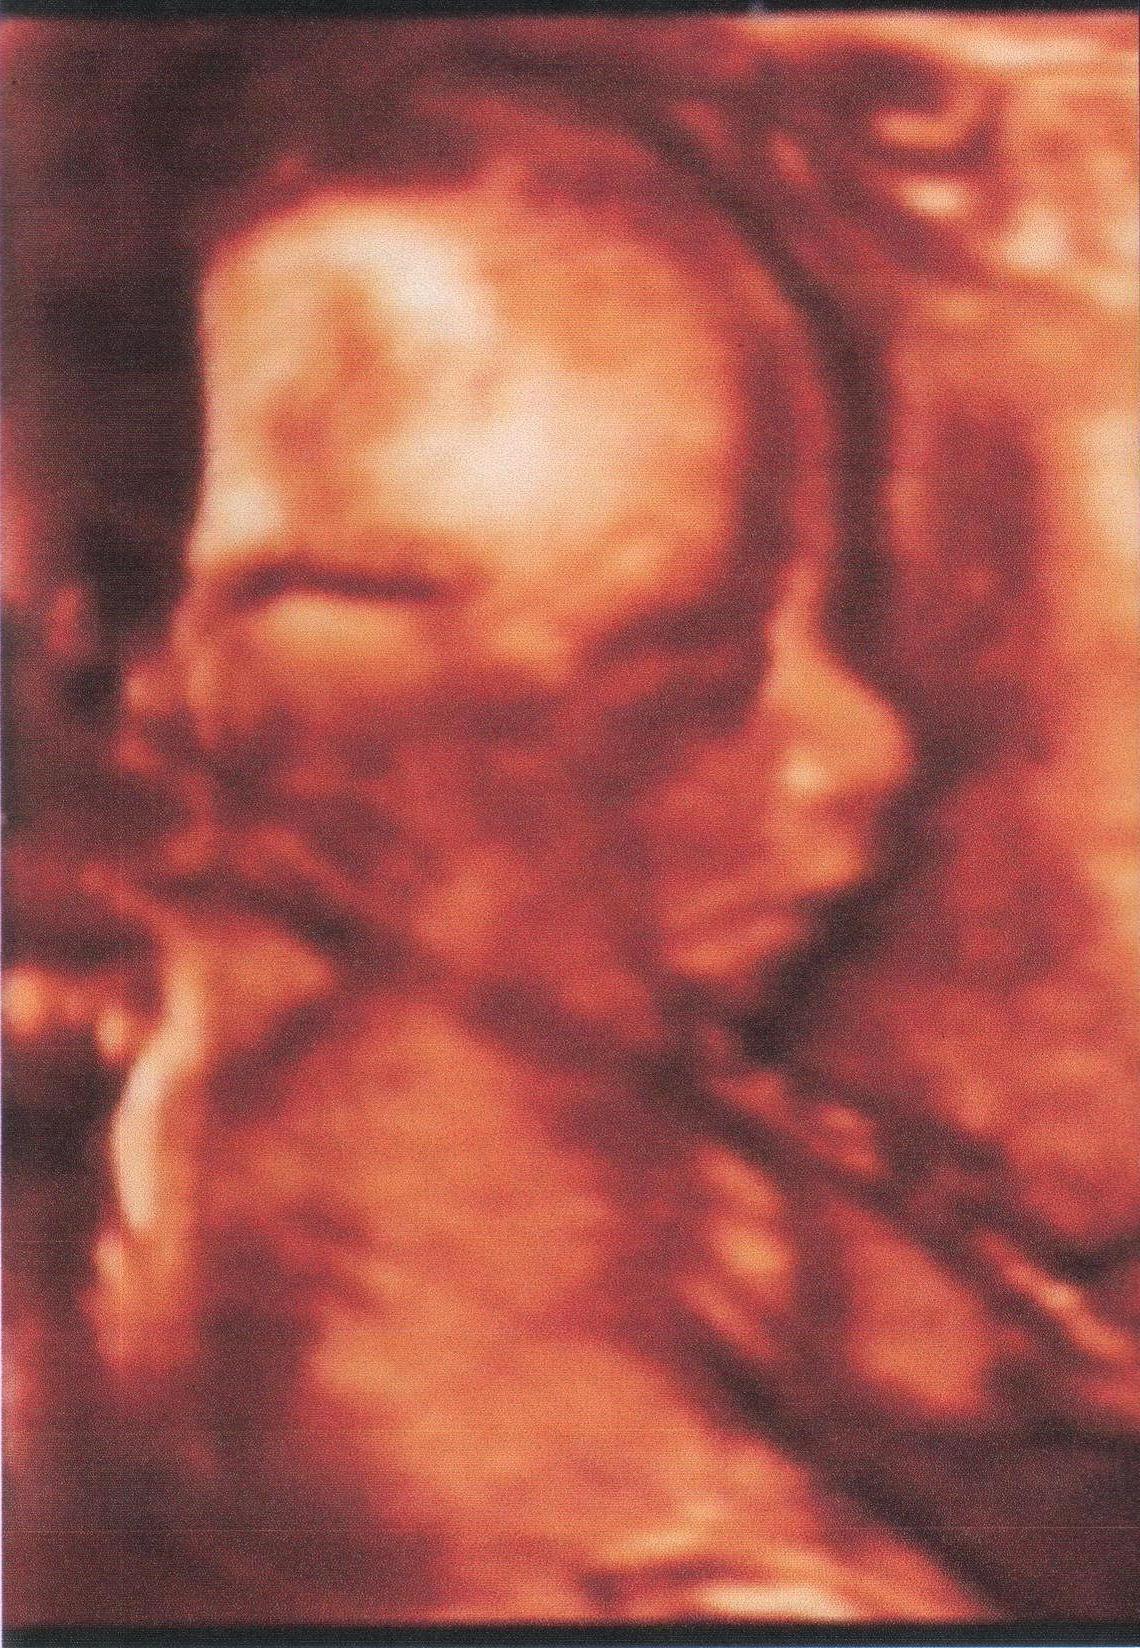

.. ну вот,врач уволилась, ждать 2 недели? нет, спасибо,мы пойдем платно на 3Д узи!

1 октября

привеееет! какой ты хорошенький,и как на Егорку похож! врач "у вас мальчик! какой прелестный мальчик!а вы кого хотели?!" мммм,ну так то девочку,но мальчику рады не меньше,лишь бы здоровый! а как у папы светятся глаза,улыбка вон до ушей!